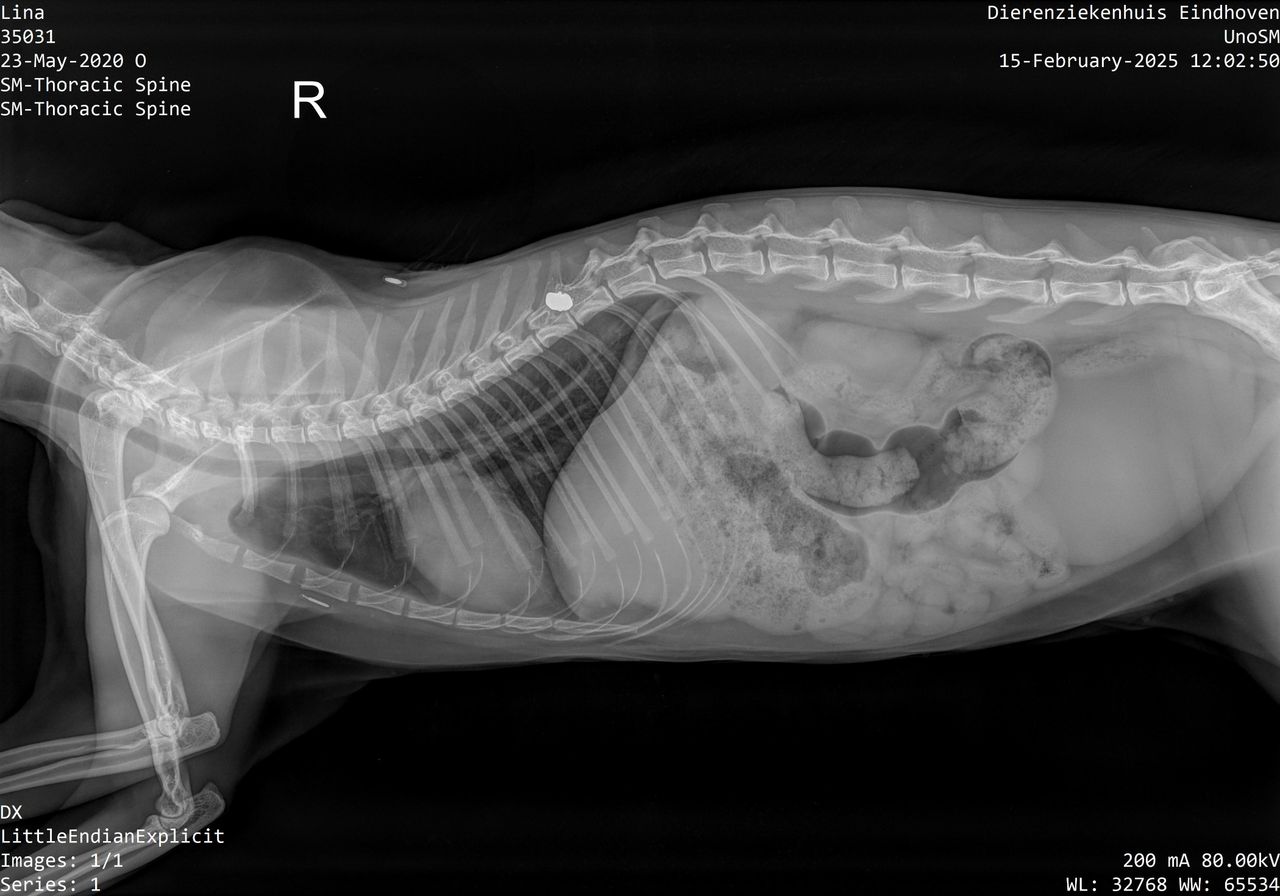

Lina is opgenomen in Dierenziekenhuis Eindhoven, waar de dierenarts een klein, verdacht gaatje in haar nek zag. Na een röntgenscan bleek daar een kogeltje in te zitten. Maar uit dit onderzoek bleek dat er nog meer met het katje aan de hand was, er zou ook nog eens vloeistof tussen haar organen zitten.

Lina moest eerst - in een speciale kliniek in Vught- met spoed worden geopereerd voor deze overtollige vloeistof, voordat er naar het kogeltje kan worden gekeken. Inmiddels is Lina thuis om van de eerste operatie te herstellen. Ze is op dit moment verlamd aan haar achterpoten, maar het gaat volgens haar baasje 'iedere dag een beetje beter'. "Zo drukken we bijvoorbeeld om de zoveel tijd op haar pootjes, om het te stimuleren. Ze begint nu wel wat terug te drukken", vertelt hij. "De pootjes echt bewegen zit er helaas nog niet in."

Na het herstel van de eerste operatie, moet gekeken worden of het kogeltje wordt weggehaald. Volgens de specialist in Vught is het een riskante operatie en is het mogelijk dat het kogeltje alles op zijn plek houdt. Het verwijderen zou dan meer kwaad dan goed doen.